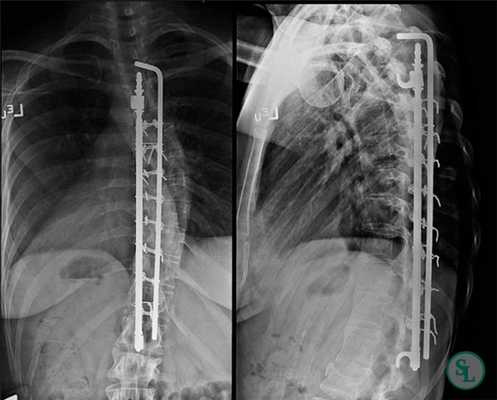

Способ Котреля-Дюбуссе

Эра становления современной деформаций позвоночника началась в 1983 году, когда Cotrel и Dubousset выполнили операцию пациентке, страдавшей болезнью Friedreich, инструментарием собственной разработки (CDI). Система (CDI) была представлена стержнями с резной поверхностью, на которые фиксировались крючки и винты в различных положениях, на различных уровнях и с различной степенью ротации. Предложена модифицированная техника трехмерной коррекции сколиоза, основанная на использовании транспедикулярной фиксации и выполнении дополнительного деротирующего маневра на сегментарном уровне. Этот метод фиксации позвоночника осуществлялся путем коррекции с сегментарной селективной дистракцией и компрессией, и деротационным маневром стержня на вогнутой стороне и обеспечивал коррекцию сколиотической и кифотической деформаций лучше, чем предыдущие методы.

Стандартным хирургическим вмешательством при сколиозе является одномоментная дорсальная коррекция деформации с костной пластикой. Коррекция должна преследовать исправление фронтального и сагиттального баланса и формирование прочного спондилодеза.

Если процедура выполнена правильно и точно, она позволяет выровнять ось позвоночника на 50–90%. Достоинством метода также является отсутствие необходимости в подавляющем большинстве случаев носить корсет в послеоперационном периоде.